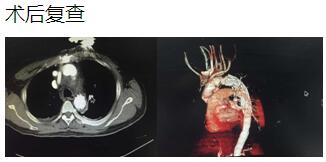

患者是一位48歲中年男性,因胸痛1小時(shí)入院,我院CT提示主動(dòng)脈夾層累及胸、腹主動(dòng)脈全層,診斷為主動(dòng)脈夾層(D ebaKey I型)?;颊卟∏槲V?,手術(shù)治療是挽救其生命的唯一希望。為了挽救病人生命,經(jīng)過(guò)麻醉科、手術(shù)室、體外循環(huán)組的術(shù)前充分討論,心胸外科廖金文主任、廖承輝副主任帶領(lǐng)團(tuán)隊(duì)決定為其施行復(fù)雜而高難度的淺低溫停循環(huán)下“孫氏手術(shù)”。術(shù)中見主動(dòng)脈全程及三分支受累,右冠受累,冠脈開口受壓狹窄,予以行“升主動(dòng)脈 主動(dòng)脈弓置換 降主動(dòng)脈術(shù)中支架置入術(shù)”,團(tuán)隊(duì)成員歷經(jīng)約10個(gè)小時(shí)的奮戰(zhàn),手術(shù)順利完成。術(shù)后六小時(shí)患者意識(shí)完全清醒,現(xiàn)在已完全康復(fù)。